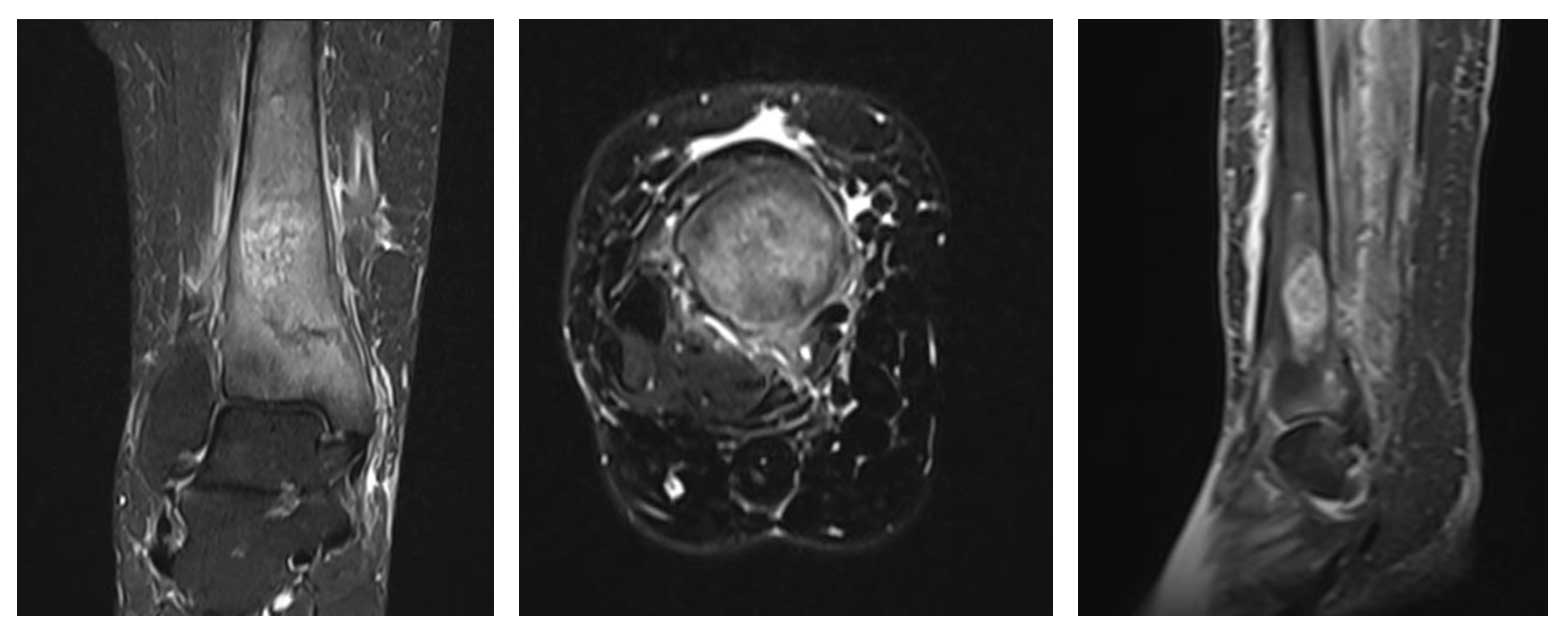

Kadın hasta, ayak bileği çevresinde ağrı ve şişlik şikayetleriyle başvurdu. Yapılan radyolojik tetkikler ve biyopsi sonucunda distal tibia yerleşimli osteosarkom tanısı konuldu. Taramalarında metastaz saptanmadı ve cerrahi tedavi planlandı.

Ameliyat Öncesi: MR’da aynı lokalizasyonda tümör dokusu ve çevreleyen yaygın ödem görülmekte.